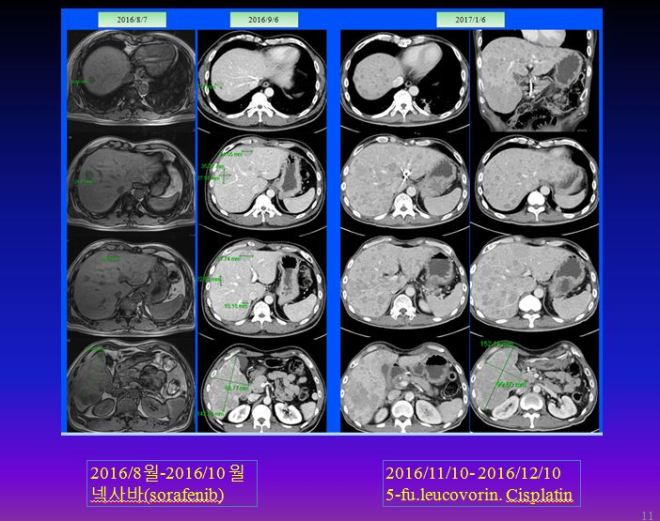

이후 8월 7일 MR상 거의 간의 우엽에 14cm 가까이 되는 종양이 보이는데 그 사이에 암이 3cm 이상 자랐다는 이야기가 된다. 이후 K 의료원에서 넥사바라고 불리우는 sorafenib을 2달 동안 사용하였다. 이후 결과는 간의 종양은 약간 자랐다고 볼수 있고 간암의 수치는 많이 떨어졌다고 하였다.

가족들은 간암의 수치가 좋아져서 간의 종양도 많이 줄었을 것으로 기대하였으나 크기는 오히려 약간 커지는 경향을 보이자 많이 실망을 하였고, 이후 주치의는 소음인약인 5-fu. leucovorin.cisplatin 등 folfox 공식을 사용하여서 2016년 11월부터 12월까지 한 달간을 사용하였다.

이후 주치의는 folfox 공식에 준하는 cisplatin 5-fu. leucovorin을 결합 사용하였는데 이는 모두 소음인 약물로 소음인에게는 유효하지만 태음인에게는 반응을 하지 않거나 더 빨리 암을 진행시킬 수있다. 암은 유지시키는 것만으로도 중요한데 암 크기가 다소 늘어났다고 하여서 소음인 약으로 바꾸고 나서 결국은 매우 악화되어서 며칠 전 본원에 내원하였다. 이를 비교해 보면 다음과 같다.

9월 사진만 해도 약간씩 증가된 것으로 보이는데 한 달간 소음인 약물로 추론되는 항암제를 사용하고 나서 간 전체가 무수히 많이 보이는 점들로 꽉 차게 되었다. 여기다가 또 무슨 약침이니 하는 요법을 하는 도중에 본원에 내원하게 되었다. 환자는 나이가 아직 젊다는 것 빼놓고는 무엇하나 건질 것이 없는 정도로 상태가 나빴지만 어느 한의사 선생님이 소개해 주어서 내원하였다 한다.

아래의 그림과 같이 folfox 3차에 다발성으로 전간에 작은 nodule들이 퍼지는 것을 볼 수 있다.